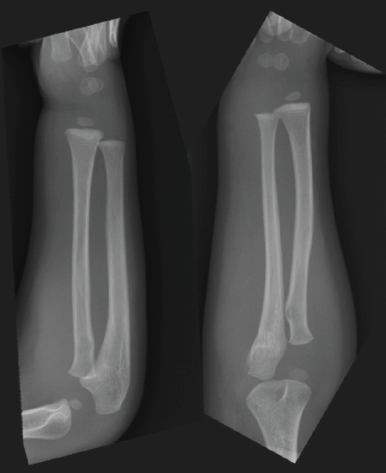

Acute Forearm Compartment Syndrome in a Toddler Caused by Hematoma without Fracture: A Case Report

Yasushi Naganuma , Hiroshi Satake , Norio Fukuda , Michiaki Takagi